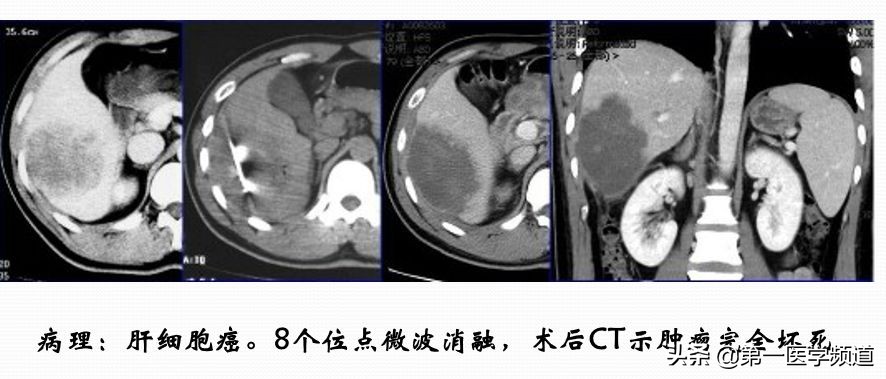

微波手术相对消融来说,比较简单,因为大部分的病人都是单针的处理,在临床上用得也非常广泛,比如应用于肝癌、肺癌、乳腺癌、胰腺癌、前列腺癌、骨肿瘤、子宫肌瘤等。它安全性比较高,而且价格适中。

这是一个典型的微波治疗肝癌患者的案例。肝脏内比较大的肿块,接近5cm左右,我们通过8个位点做消融治疗,取得比较好的效果,术后肿瘤完全坏死。